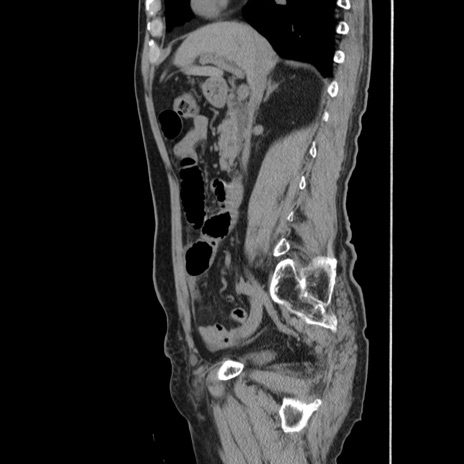

症例24(矢状断像)

【症例】80歳代男性

【主訴】左側腹部痛、嘔吐

【現病歴】本日早朝より左腹部に痛みあり。昼頃嘔吐認めたため、救急要請。

【既往歴】直腸癌(Mile手術)、胆摘

【身体所見】意識清明、BT 35.9℃、BP 221/93mmHg、SpO2 97%(RA) 、腹部:左ストーマ周囲に限局性の腹部膨隆あり。 膨隆部自発痛・圧痛あり・軟。

【データ】WBC 7700、CRP 0.09